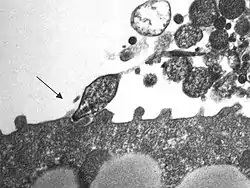

Patogenia e inmunidad

M. pneumoniae es un patógeno extracelular que se adhiere al epitelio respiratorio mediante una estructura de anclaje especializada, que se forma en un extremo de la célula. Esta estructura está constituida por un complejo de proteínas para adherencia, en la que destaca la adhesina P1 como la más importante. Las adhesinas interactúan de manera específica con los receptores de glucoproteínas sialidadas en la base de los cilios de la superficie de las células epiteliales (así como en la superficie de los eritrocitos). A continuación tiene lugar la ciliostasis, tras la que son destruidos en primer lugar los cilios y posteriormente las células del epitelio ciliar. La pérdida de estas células interfiere en el aclaramiento normal de las vías respiratorias superiores y permite que las vías respiratorias inferiores se contaminen con microorganismos y sufran una irritación mecánica. Este proceso es el responsable de la tos persistente que tienen los pacientes con enfermedad sintomática.